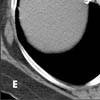

A CT image below the level of the heart (E) shows extensive venous collaterals that extend to the inferior vena cava (arrows). Venous collaterals extending to the inferior vena cava are also evident on another slice in the upper abdomen (F, arrows).

Figure E